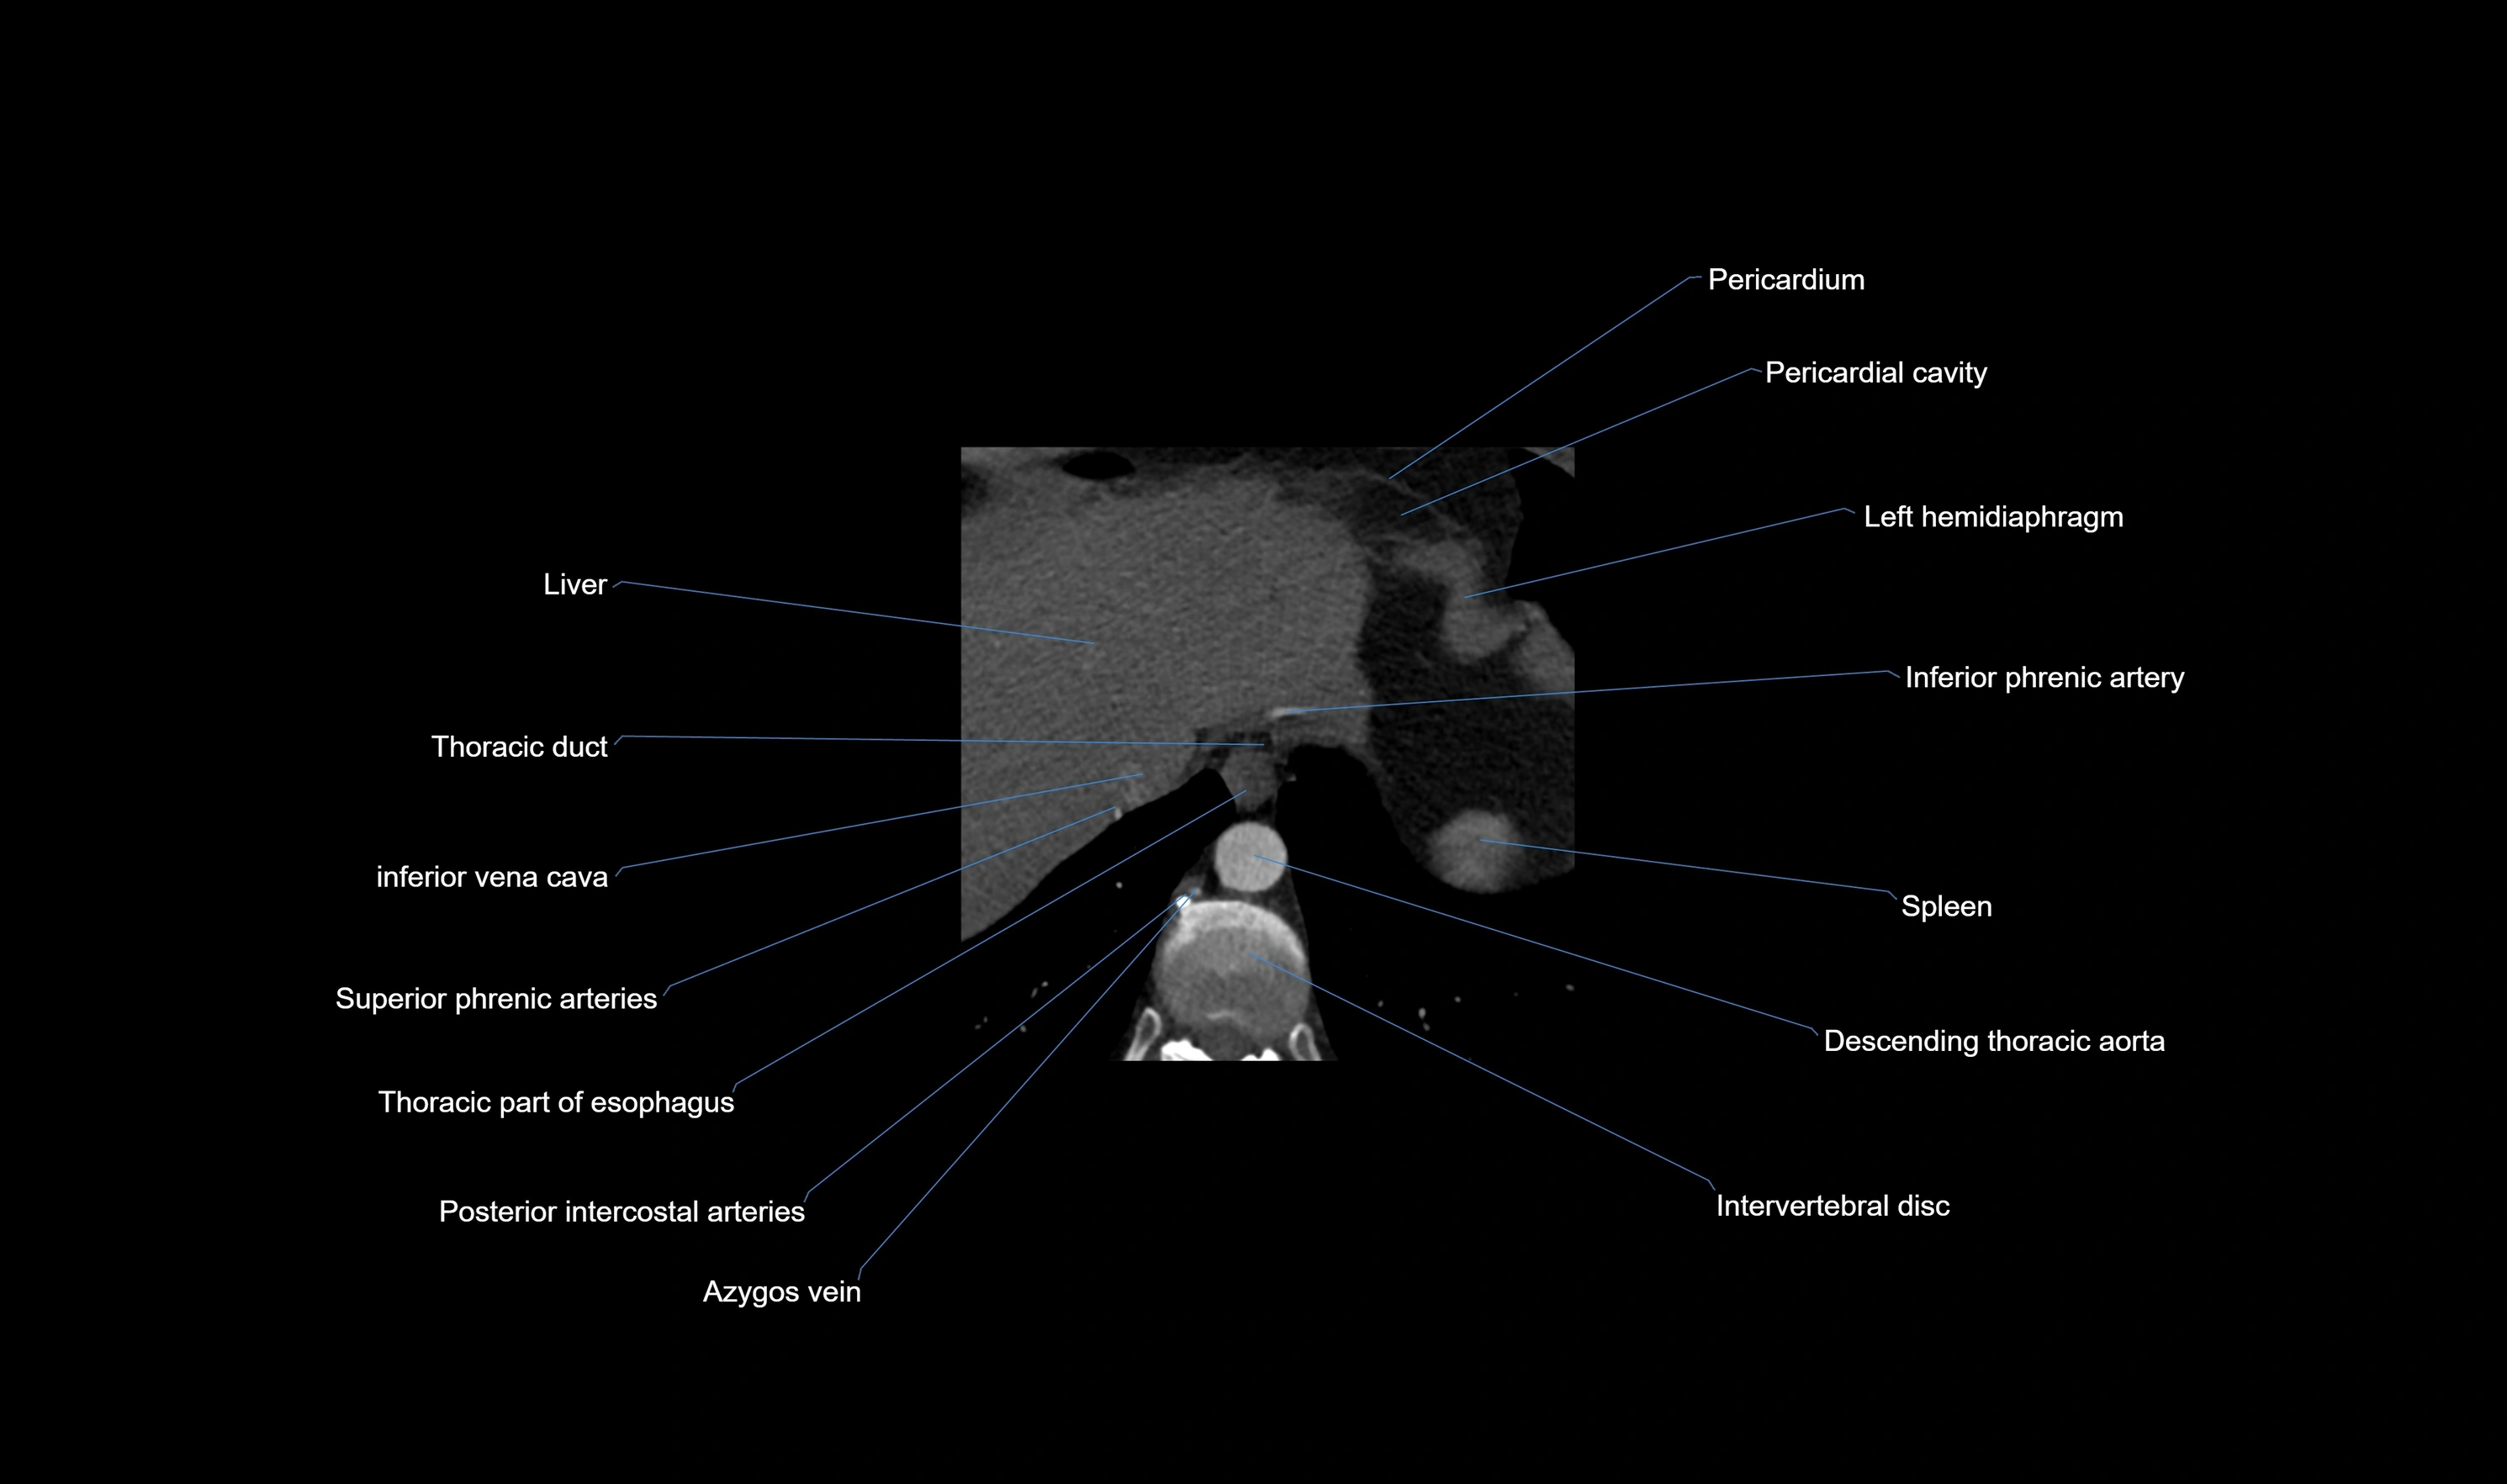

CT images